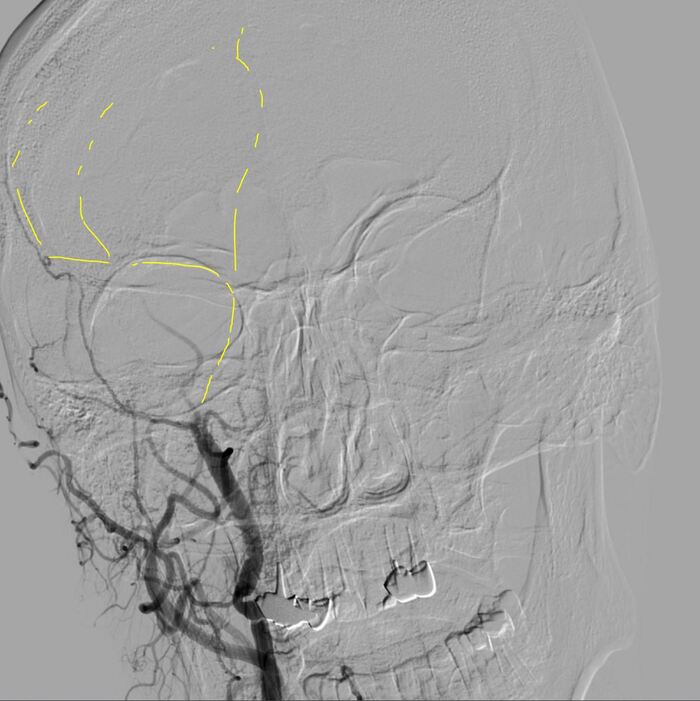

Делаю третью попытку...

Да уж... Но что то подсказывало, "еще разочек" )) Ок. давай еще попробуем...